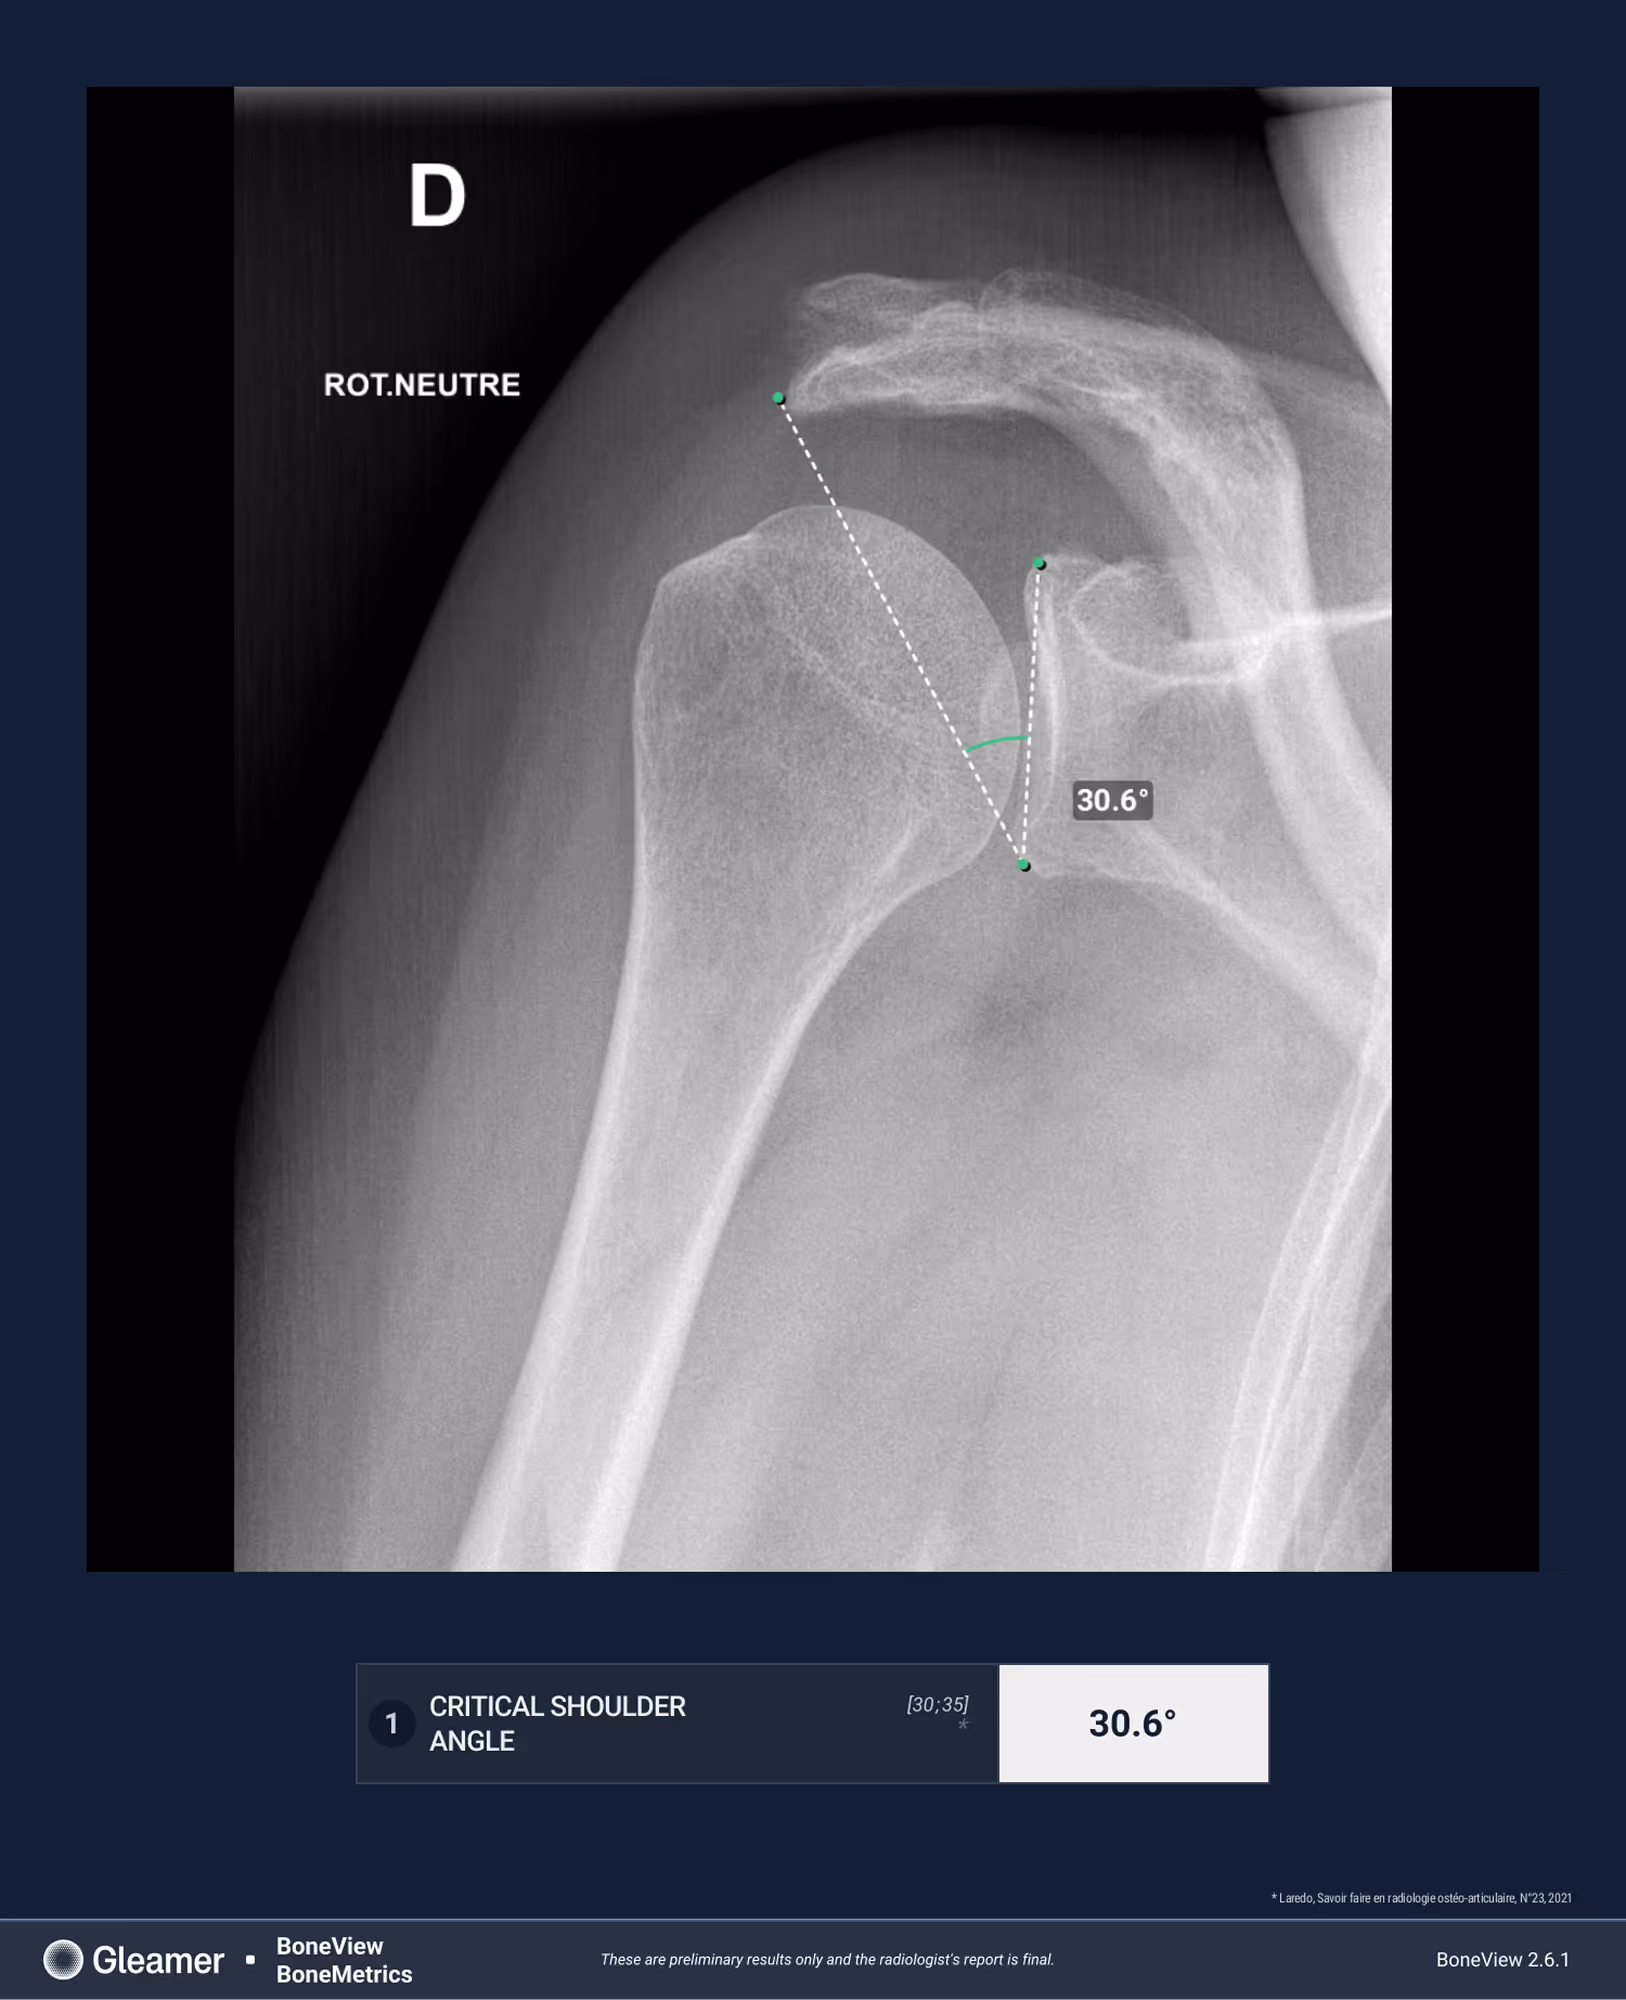

A 64-year-old female presenting with persistent left shoulder pain, undergoing evaluation prior to potential acromiosplasty.

Results

BoneMetrics found a critical shoulder angle within normal limits.

Frontal

Critical shoulder angle (CSA)